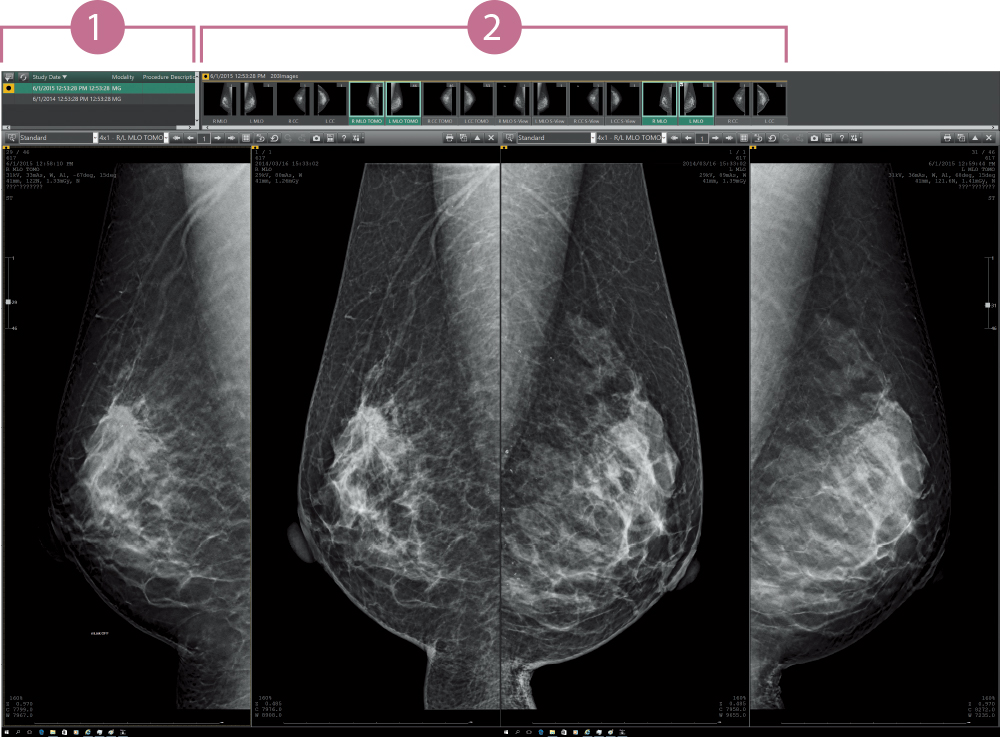

Los resultados de varios exámenes de una paciente se muestran en una lista. Los usuarios pueden cambiar la imagen mostrada por una de las imágenes seleccionadas.

La ventana de miniaturas permite a los usuarios ver instantáneamente todas las imágenes tomadas para cada examen individual en una sola vista. Cada imagen puede seleccionarse y mostrarse fácilmente arrastrando y soltando.

Función de captura instantánea: Las condiciones de visualización, el orden y el factor de escala de cada imagen pueden almacenarse en el ordenador y volver a visualizarse con las mismas condiciones.

El sistema de informes de mamografía admite diferentes estilos de lectura, como la “lectura simple”, la “lectura doble”, etc. La operación de arrastrar y soltar desde el visor a la aplicación de informes está disponible para agregar imágenes.

Los elementos mostrados en la lista pueden ser acotados por fecha, modalidad o algún otro aspecto utilizando la función de filtrado. En la lista se muestra el tipo de exámenes realizados como Tomo/Biopsia y la disponibilidad de informe.